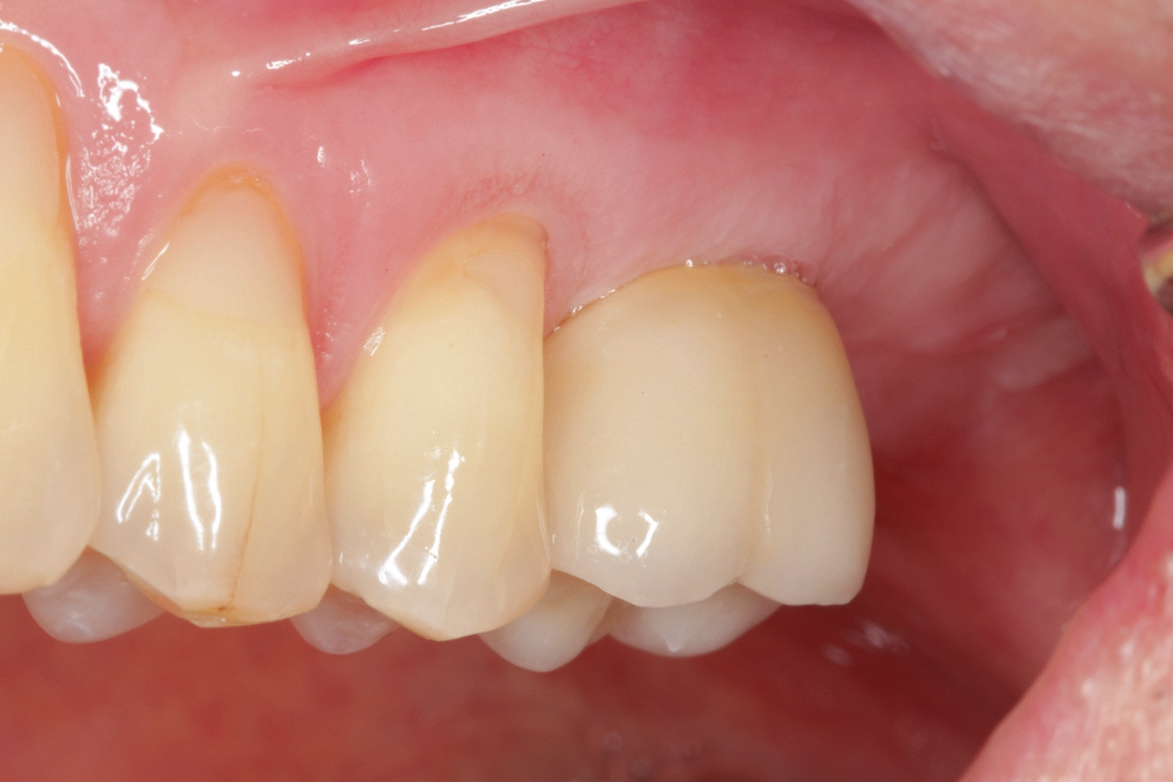

60-jähriger, männlicher Patient mit seit etwa acht Jahren bestehender Freiendsituation in regio 26/27. Drei Jahre zuvor wurde auf Position 36 ein PURE Monotype erfolgreich eingesetzt und prothetisch versorgt. Insgesamt ausgezeichnete Mundhygiene und absolut reizfreie Situation an 36. Der Wunsch des Patienten war nun die Versorgung der Position 26 mittels eines Keramikimplantates ohne größere chirurgische Intervention. Nach Anfertigung der dreidimensionalen Aufnahme (DVT) stellten sich ein ausreichendes transversales Knochenangebot und eine vertikale Höhe von ca. 5 – 6 mm zur Kieferhöhle dar, so dass ein interner Sinuslift und die Verwendung eines zweiteiligen Implantates geplant wurden. Das geringe vertikale Knochenangebot und die reduzierte Qualität verglichen mit dem Unterkiefer hätten bei Verwendung eines einteiligen Implantates mit transgingivaler Heilung ein Risiko für die erfolgreiche Osseointegration dargestellt. Zur Vorbereitung wurde die leichte basale Schleimhautschwellung beim Hals-Nasen-Ohren Arzt abgeklärt und der Patient führte täglich Nasenspülungen durch.

Nach lokaler Anästhesie wurden ein Kieferkammschnitt und eine nur minimale Mobilisation des Mucoperiostlappens durchgeführt. Beim internen Sinuslift nach Summers wird die Pilotbohrung bis ca. 1 mm vor die Begrenzung der Kieferhöhle vorgenommen und je nach Knochenangebot und Qualität mittels verschiedener Osteotome (Institut Straumann) weiter aufbereitet. Unabdingbar ist dabei die regelmäßige Kontrolle der Unversehrtheit der Schneider‘schen Membran durch einen „Nasenblasversuch“. Nach erfolgreicher Aufbereitung des Lagers konnte ein Implantat Größe 4,1/10 mm sehr gut primärstabil inseriert werden, anschließend primärer Wundverschluss mittels 5/0 monophiler Naht. Nach vier Monaten erfolgte die minimalinvasive Freilegung und Applikation des Gingivaformers.